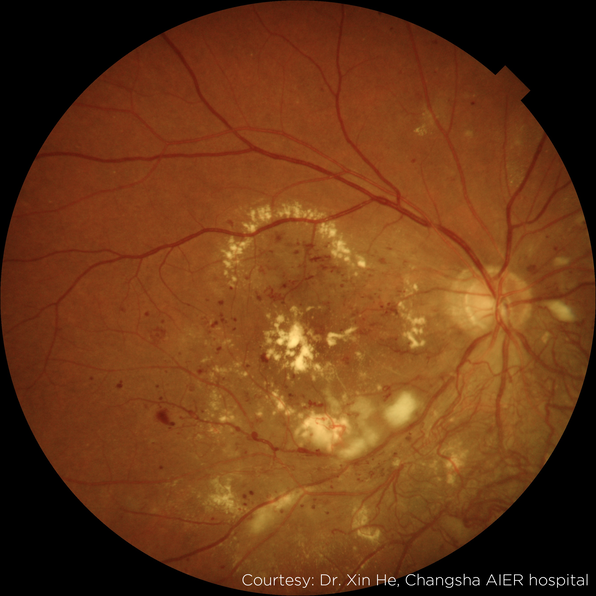

Image Gallery